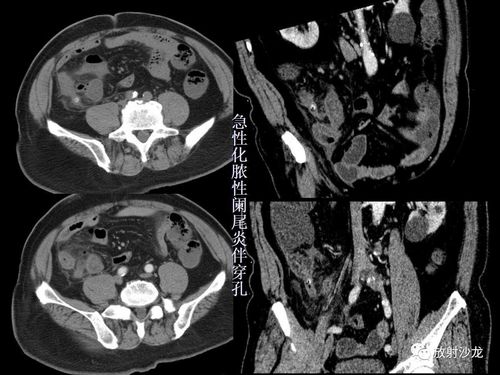

精品讲座急性阑尾炎的ct诊断

ppt急性阑尾炎的ct诊断

全面讲解正常阑尾和阑尾炎的ct表现

开课了急性阑尾炎的ct诊断及鉴别诊断

打基础 | 急性阑尾炎 ct 诊断

急性阑尾炎CT图片